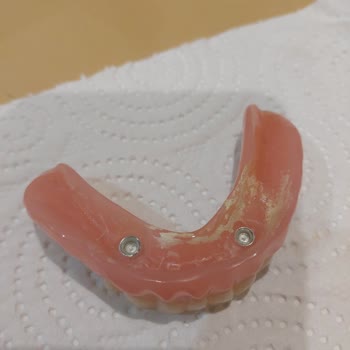

Adana Seyhan’daki Fatma Kemal Timuçin Diş Hastanesi’nde, doktor **** tarafından yapılan implant tedavim sırasında ve sonrasında hem sağlık açısından hem de davranış açısından çok olumsuz bir süreç yaşadım. İmplantlarımdan rahatsız olduğumu, sorun yaşadığımı doktora ilettiğimde, kendisi bana hakaret ...

devlet, implant